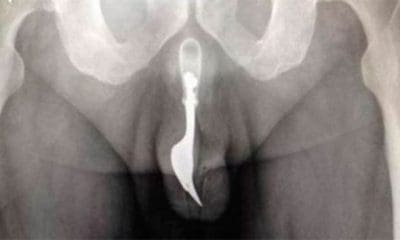

Una increíble visita de urgencia tuvieron que atender médicos del hospital de Canberra (Australia) luego que llegara un hombre de 70 años con un intenso dolor. El sujeto...